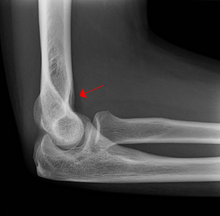

A subtle radial head fracture with associated positive sail sign

On an elbow X-ray, the fat pad sign, also known as the sail sign, suggests an occult fracture. Its name derives from the fact that it has the shape of a spinnaker (sail).[1] It is caused by displacement of the fat pad around the elbow joint. Both anterior and posterior fat pad signs exist, and both can be found on the same X-ray.

In children, a posterior fat pad sign suggests a condylar fracture of the humerus. In adults it suggests a radial head fracture. The fat pad sign only occurs after an intra-articular fracture.

The fat pad sign is invaluable in assessing for the presence of an intra-articular fracture of the elbow. An anterior fat pad is often normal. However a posterior fat pad seen on a lateral x-ray of the elbow is always abnormal. The patient will be unable to flex their elbow and requires orthopaedic input.[2]